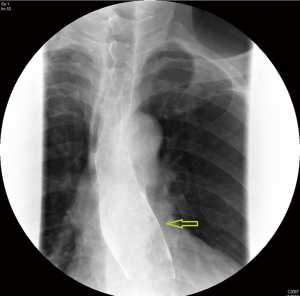

Upper gastrointestinal tract endoscopy disclosed a giant submucosal mass with a smooth surface that was located 18 to 40 cm from the incisors. Multiple biopsy specimens revealed inflamed mucosa with hyperaemia. There was no evidence of malignancy. Ultrasonic gastroscopy disclosed a giant protrusion of the esophagus located 18 cm from the incisors that originated from the submucous and was suspected to be a neurofibroma because of its homogeneous and hypoechoic lesion with clear margins. Distal esophagus and gastroesophageal junction was normal (Figures 1,2). A barium swallow showed a large intraluminal mass of the upper esophagus and compensatory dilatation of the proximal esophagus. A slightly irregular mucosal surface indicated a probable benign esophageal tumor (Figure 3). The patient underwent cervical, cardiac and abdominal ultrasound, which were unremarkable. Blood counts, biochemistry values and tumor markers levels were all found to be within normal limits.